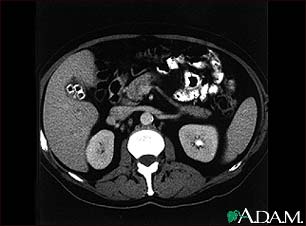

Cholecystolithiasis

Cholecystolithiasis. CT scan of the upper abdomen showing multiple gallstones.